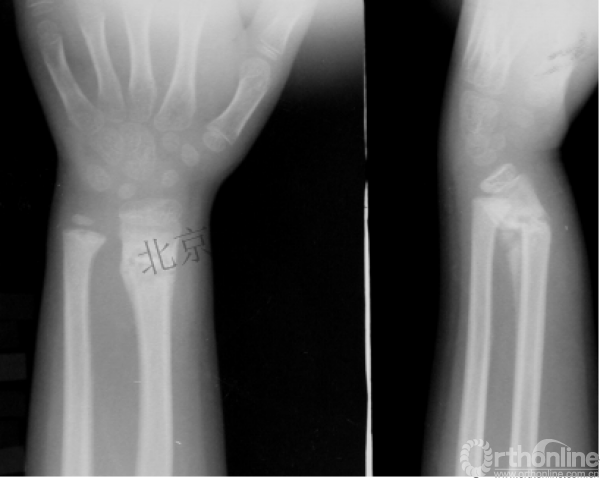

病例分享一

男孩 、5岁,初次骨折于2007年7月。

术后2年→再骨折→再次手术

钢板固定后一年

取板后再骨折→TEN

TEN取出后2个月